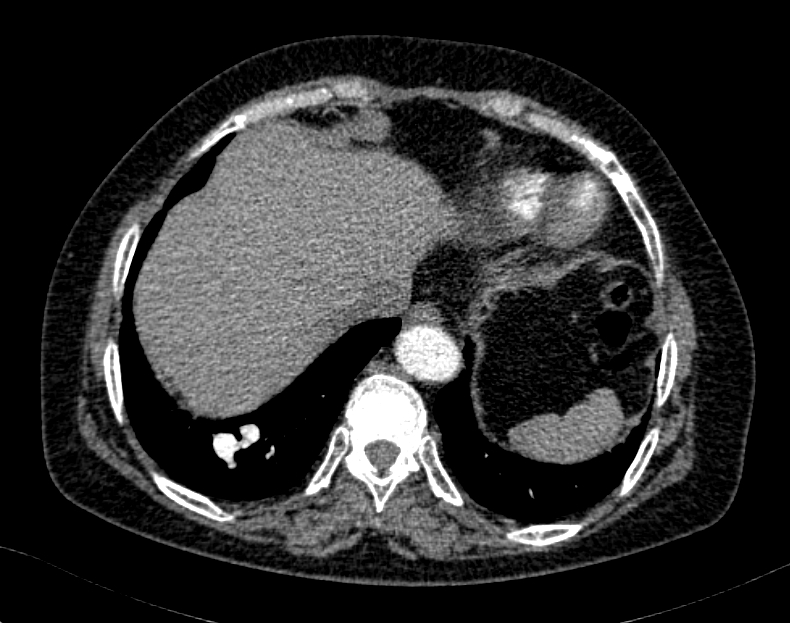

63¼¼ ¿©È¯

°©»ó¼±¾ÏÀ¸·Î ¼ö¼ú ¿¹Á¤À¸·Î, ¼ö¼ú Àü evaluation »ó¿¡¼­ CXR abnormality ÀÖ¾î

chest CT ±îÁö ½ÃÇàÇÏ¿´½À´Ï´Ù.